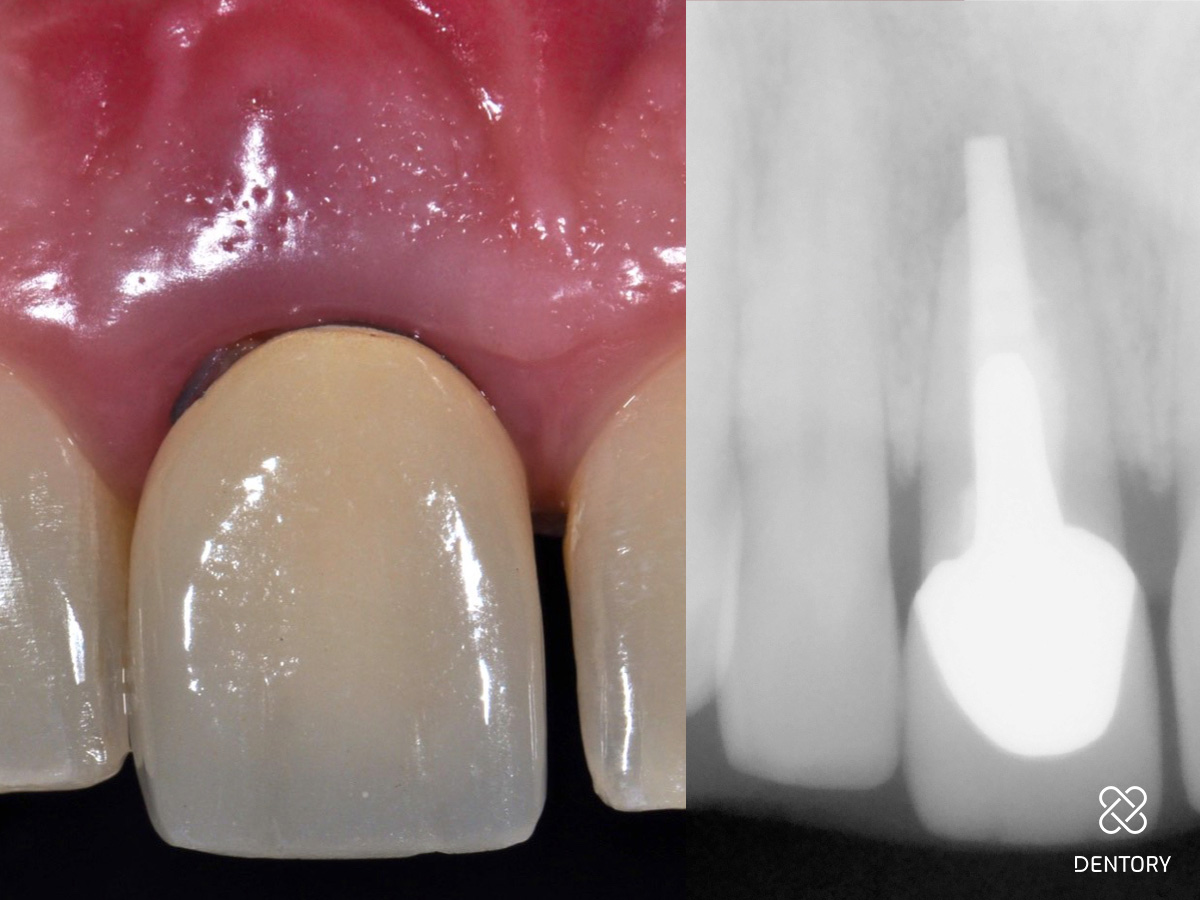

Heilung: Acht Wochen nach dem operativen Eingriff. Das Gingivatransplantat ist vollständig integriert. Die Gewebekontur konnte gut erhalten werden.

Abbildung 17

Heilung: 8 Wochen Post-OP - frontale Ansicht

Abbildung 18

Heilung: 8 Wochen Post-OP - okklusale Ansicht